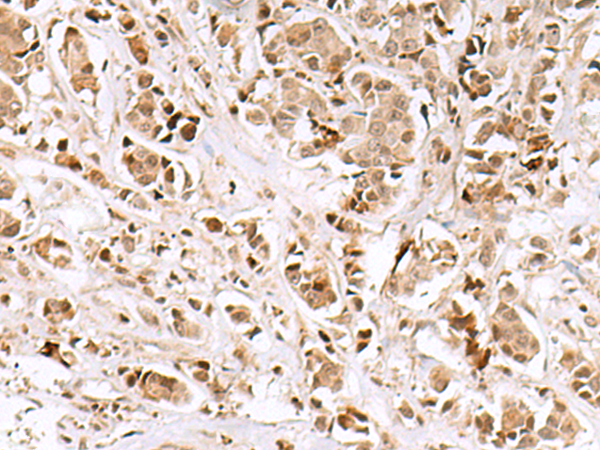

IHC 1/50-1/300 Human,Mouse,Rat

The INSM1 (Insulinoma-associated protein 1) antibody is a valuable tool in studying and diagnosing neuroendocrine neoplasms. INSM1. a zinc-finger transcription factor, plays a critical role in neuroendocrine differentiation and embryonic development, particularly in the nervous system, pancreas, and endocrine tissues. First identified in insulinomas, it is highly expressed during embryogenesis but largely silenced in most adult tissues, except in neuroendocrine cells. Reactivation of INSM1 has been observed in various neuroendocrine tumors (NETs), including small cell lung carcinoma, medullary thyroid cancer, and neuroblastoma, making it a specific biomarker for these malignancies.

The INSM1 antibody detects nuclear expression of the INSM1 protein via immunohistochemistry (IHC) or immunofluorescence. Its clinical utility stems from high sensitivity and specificity for NETs, often outperforming traditional markers like chromogranin A and synaptophysin, especially in poorly differentiated cases. Additionally, it aids in distinguishing NETs from non-neuroendocrine cancers, supporting accurate classification and treatment planning. Research also employs INSM1 antibodies to explore developmental biology, tumorigenesis mechanisms, and potential therapeutic targets. Overall, INSM1 antibodies bridge diagnostic precision and molecular research in neuroendocrine pathology.